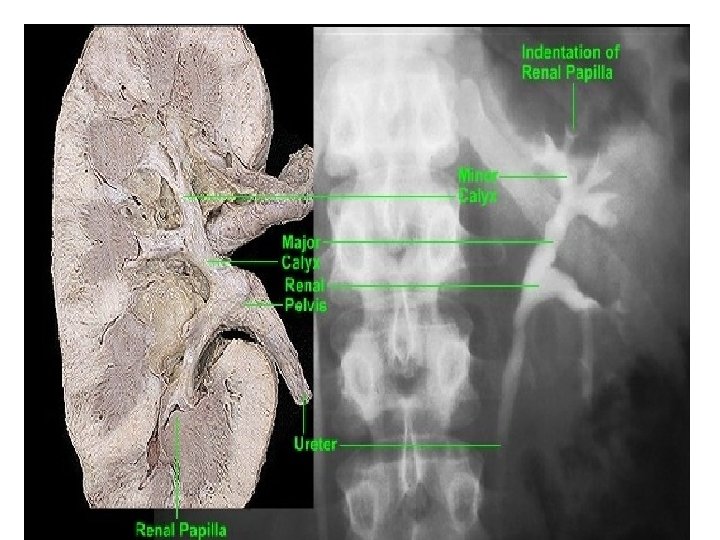

STRUCTURE OF HILUM OF KIDENEY(V. IMP)